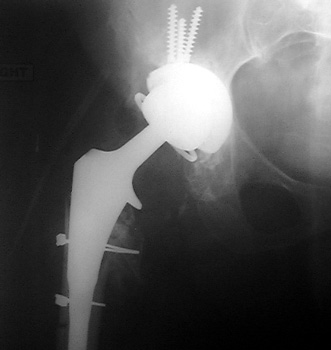

Dislocated femoral component secondary to steep acetabular cup inclination, pre and post revision. Note constraining ring about femoral head, which helps maintain head in cup